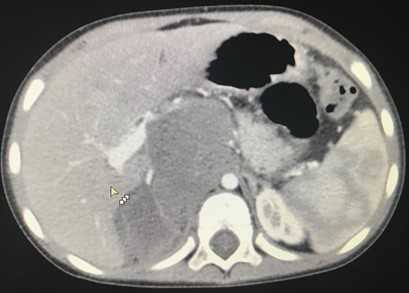

Компьютерная томография более детально дает информацию об анатомическом отношении опухоли к окружающим тканям и органам, позволяет оценить структуру опухоли (рис. 5).

Рис. 5. КТ нейрогенного образования забрюшинного пространства справа